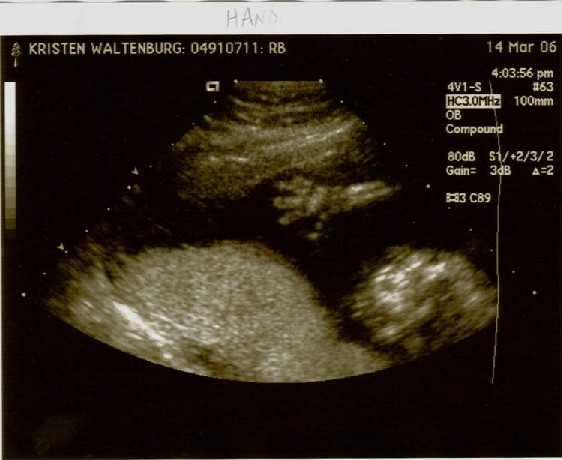

After following a strict schedule of how much water to drink, when to drink it, when to pee and when not to pee, Colby and I arrived at Kaiser for our big ultrasound appointment! The BIG day, when we would find out if we have a pink or blue bun in the oven!! While pacing up and down the aisle in a desperate attempt to stay in control of my bladder, my mom, Colby’s mom and his sisters join us for the long awaited peek. Finally! My name is called and I’m provided some relief as I lie down on the chair in the dark room. The nurse squirts some gel on my belly, which I was grateful to realize they warm it on this floor! She proceeds with the ultrasound, taking pictures for the doctor for about 20 minutes. I didn’t get a peek until the others were invited in. We saw distinct hands and feet, a big alien head, even an ear… but what we really wanted to see was obstructed by two little legs, crossed at the ankles. No angle could seem to enlighten us!! So, the nurse admitted that when she was taking pictures on her own, she got a possible view of what she thinks are boy parts, but since she couldn’t get back under there to verify it, she said she would print that picture and leave it to our interpretation. That’s where you come in. Please take a look at the pictures below. The one labeled “Gender” is the deciding factor. Once you’ve gotten a good look, please use the “post your comment” link at the bottom of this blog, and let us know if you believe it to be a boy or girl. Profile:

Hand: